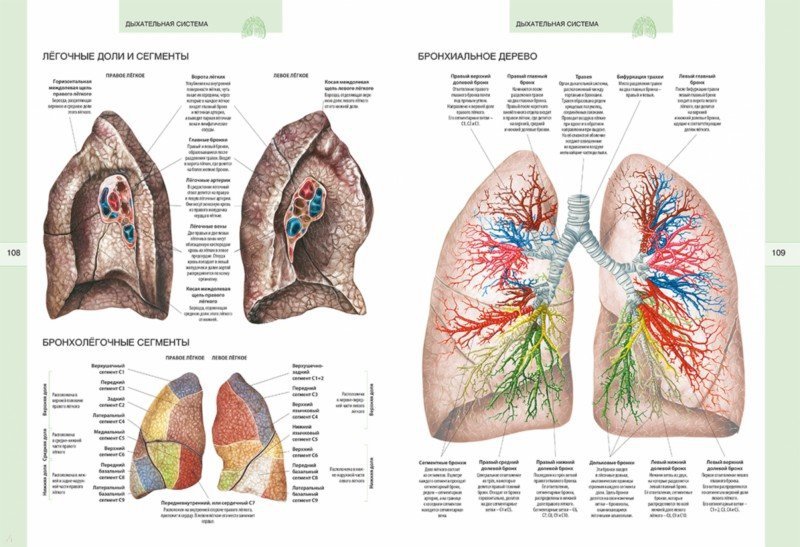

Анатомические изображения сегментов легких различных животных

Раздел: Другие животные